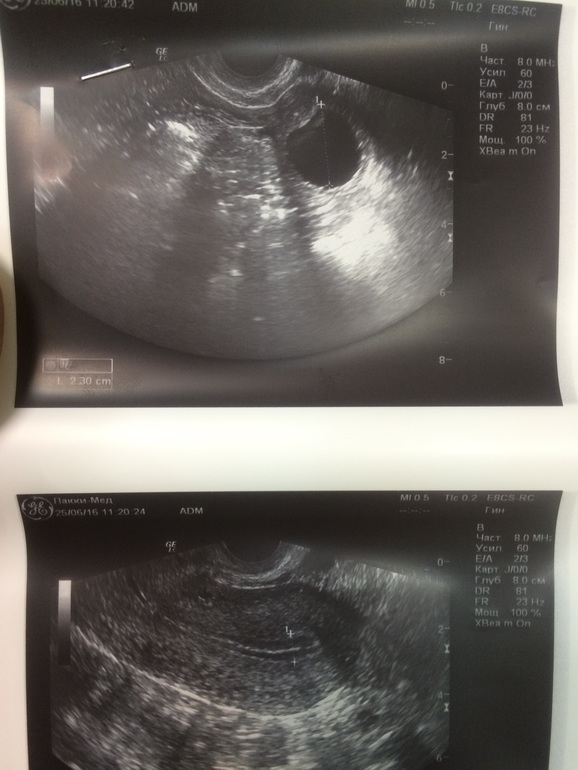

Уходила в отпуск в надежде на беременность, но в процессе пришли меськи (( было очень обидно, на днях начало у меня все болеть и тянуть, пошла я на узи а там на носу Овуля!!!! Сюрприз невероятный. Узи на 10 дц, тесты на 10 и 11

Эндик 8,3 ДФ 22 мм, ну девочки зачихайте меня ))) в отпуске не была с сентября и вот отдохнула наконец!!! Пусть все случится!!! Чудо, мы с папой тебя ждем очень!!!

о да)))ОНО пусть чудо свершится😊😊😊😊 P.S у вас рубец в матке?????

да нет ))я думала КС..на втором снимке будто рубец

прикольно😂😂😂у меня так рубец выглядит

Какой хороший фолликул, кругленький, что надо! Удачи, Кристин!! Пусть все получится!